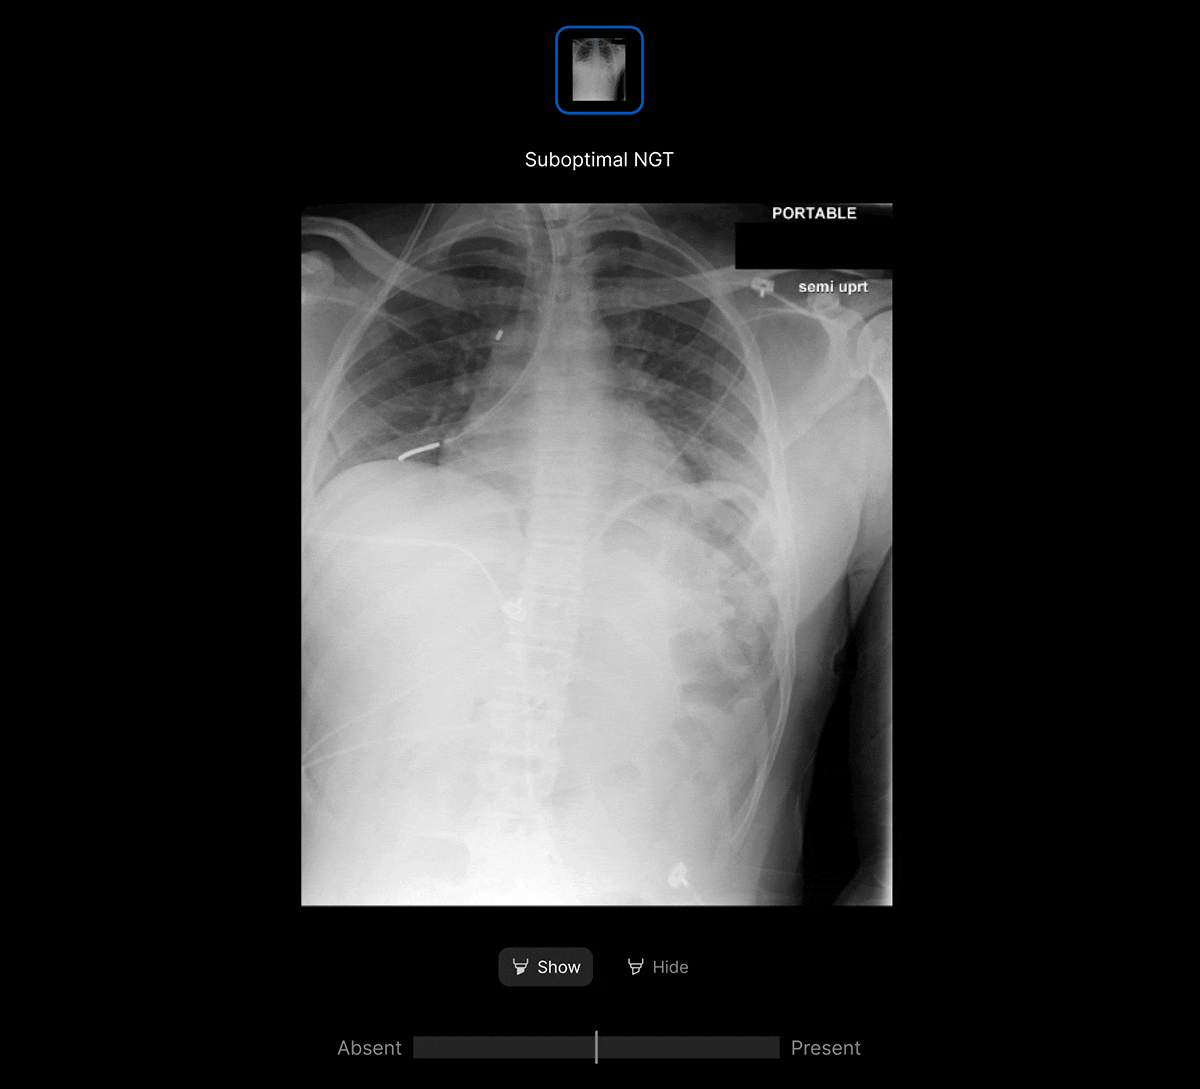

Harrison.ai chest X-ray (CXR) is a comprehensive AI solution for chest X-rays that detects up to 124 findings in under 20 seconds, boosting emergent and incidental capture while surfacing urgent cases for review first – all within the workflow you’re used to.

Accelerate care pathways with AI-powered Worklist Prioritisation. Detect up to 124 findings on chest X-ray, enabling optimised workflows across multiple use cases and care settings including radiology, emergency and acute care, lung cancer pathway, chronic care and teleradiology.

- Customisable clinical findings and thresholds to suit your workflow.

- Seamless integration with PACS and RIS.

- AI results provided within 20 seconds.